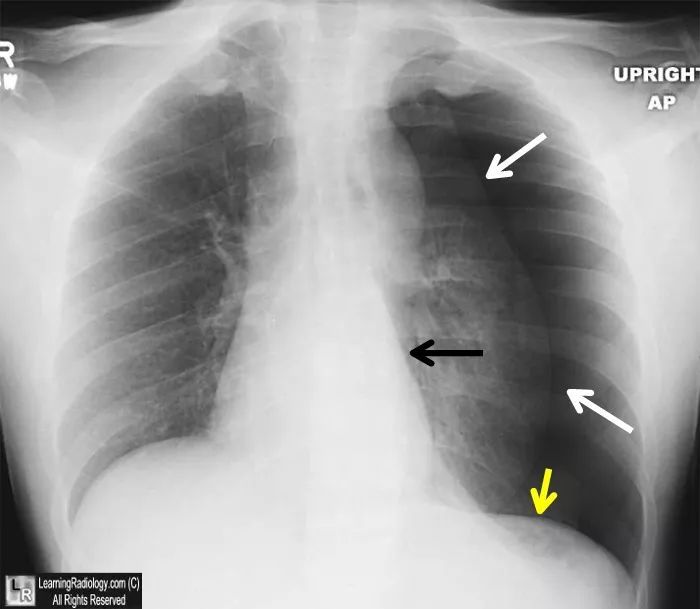

气胸平片图像

气胸的x线表现,6个病例搞定!

图文详解丨气胸的影像学表现

气胸的x线表现,6个病例帮你搞定!